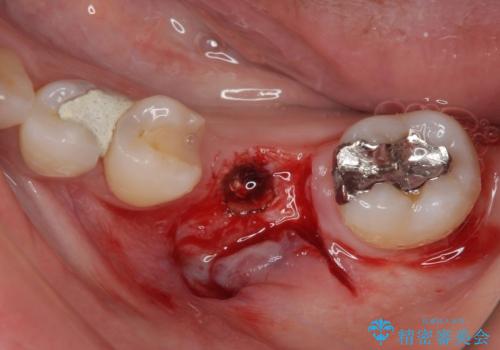

- ブリッジの歯のないところにインプラントを入れて、銀歯を白くやり替えたいと来院された患者様です。

歯の欠損している箇所にはインプラント治療をし、銀歯と仮詰めの部分はセラミックインレーにて補綴することとしました。

すべての治療の前に親知らずの抜歯も行っています。

- 外科手術のため、術後に痛みや腫れ、違和感を伴います

- 外科手術のため、術後に出血、痛みや腫れ、違和感を伴います